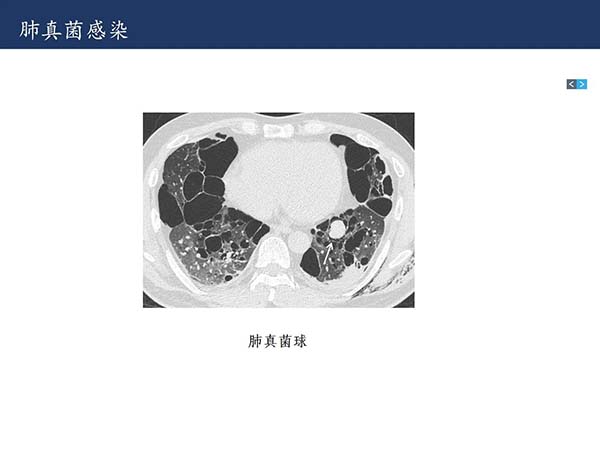

【杨柳科普】肺上皮样血管内皮瘤的影像表现